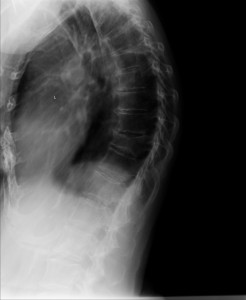

In osteoporosis, the cause is fractures in the upper or thoracic spine. The fractures are typically in a wedge shape that produces the bent forward posture. This wedge shape of an individual vertebra is a result of the front section decreasing in height relative to the back section. Usually, kyphosis occurs after multiple fractures rather than just one.